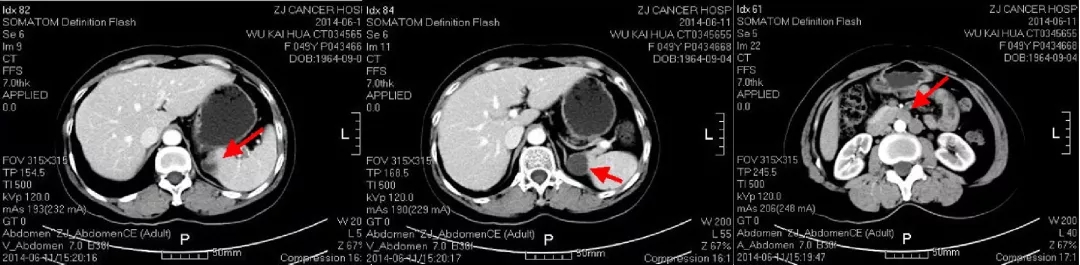

2013.5.6在我院(中国科学院大学附属肿瘤医院)检测CA125水平为298.8U/ml。CT:胸部(-),肝肾隐窝异常信号,脾脏前内方囊性占位灶,考虑转移灶;肠系膜上动脉水平、腹主动脉偏左侧结节灶;盆腔(-)。

2013.5.10 PET-CT:肝肾隐窝、脾肾间隙、脾门旁、腹膜后可见斑片状、囊实性及结节状影,实质部分FDG代谢增高,考虑转移。

2013.5.10 PET-CT检查结果